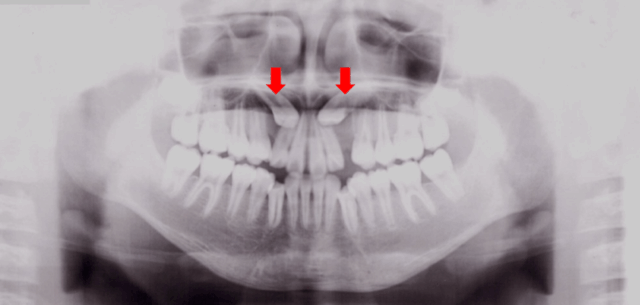

疑わしい箇所にレントゲン検査を行い、歯茎の中で起きていることを確認します。

6歳を過ぎたら1度、パノラマレントゲン(お口全体の写真)による検査をオススメします。

肉眼では問題がないように見えても、歯茎の中で犬歯が隣の歯の根にあたっています。

レントゲン検査で、このような問題を早期に発見できます。